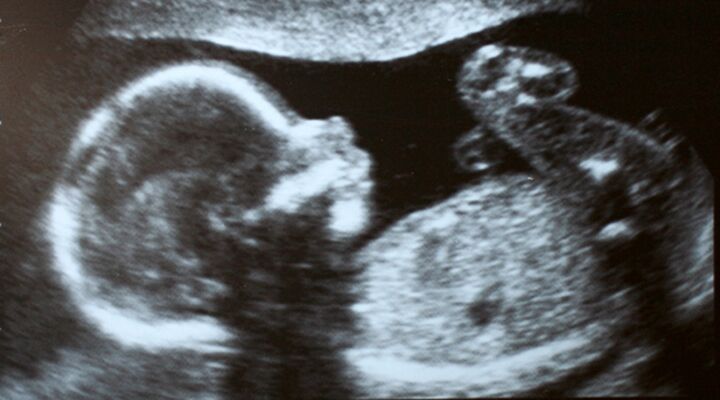

In February of last year, federal agents raided a West Philadelphia abortion clinic on the suspicion it was distributing prescription drugs illegally. What started as a routine drug bust ended with a nauseating tour through a disgusting scene one might expect to find in a Third World country—but certainly not in Pennsylvania.

The facility was filthy. Flea-infested cats roamed the hallways. There was blood on the floor, animal excrement on stairwells. The stench of urine permeated the air. Medical instruments were left unsterile. Moaning, drugged-up patients were covered with blood-soaked blankets. And the remains of 45 fetuses were strewn all over the facility, stuffed in bags, jars, plastic jugs, juice cartons—even cat-food containers. Citing “an immediate and clear danger to the public health and safety,” federal authorities quickly moved to shut down the clinic and suspend Dr. Kermit Gosnell’s medical license.

In January, a grand jury finally charged Gosnell with eight counts of murder following the wrongful deaths of one woman and seven newborn babies.

“Gosnell catered to the women who couldn’t get abortions elsewhere—because they were too pregnant,” the report charges. “Most doctors won’t perform late second-trimester abortions, from approximately the 20th week of pregnancy, because of the risks involved. And late-term abortions after the 24th week of pregnancy are flatly illegal. But for Dr. Gosnell, they were an opportunity. The bigger the baby, the more he charged” (emphasis mine throughout).

Gosnell’s preferred method of performing late-term abortions was to prescribe drugs to induce labor and delivery, which often resulted in the birth of live babies. He then murdered the newborns by severing their spinal cord with scissors—a process he referred to as “snipping.”

In one particularly gruesome case, he induced the labor of a 17-year-old girl who gave birth to a healthy, 18-inch-long, 6-pound baby boy. “This baby is big enough to … walk me to the bus stop,” Gosnell allegedly joked during the procedure. Gosnell then slit his throat and dumped the body into a shoebox.

What a priceto pay to make it easier for women to get an abortion. Since Roe v. Wade, nearly 50 million unborn babies have been killed in America. And yet our spiritual sickness is so grotesque, we want to make it easier to slaughter more innocent lives—even if it means turning a blind eye to the grisly acts of “doctors” like Gosnell.